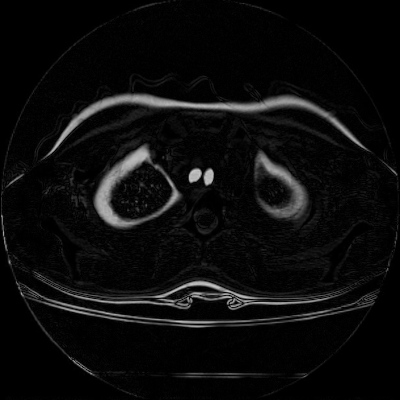

We now consider applying the proposed image registration method on real lung CT images retrieved from the National Lung Screening Trial (NLST) dataset [1]. Fig. 9(a) and Fig. 9(b) show two slices of lung CT images that we use as the source and the target (see Fig. 9(c) for the absolute intensity difference). We remark that the CT images are originally with different intensity, and so we apply an intensity histogram matching before running the registration experiment. Fig. 9(d) shows the registration result obtained by our proposed method. It can be observed that our method successfully produces a large deformation on the right lung of the source image to match that of the target image (see also Fig. 9(e) for the final absolute intensity difference). On the contrary, DDemons [47] (Fig. 9(f)), LDDMM [5] (Fig. 9(g)), Elastix [29] (Fig. 9(h)) and DROP [18] (Fig. 9(i)) all fail to produce an accurate and bijective registration result. This shows that our method is more capable of handling large deformation image registration.

We then test our method on slices of chest CT images obtained from the Open Access Biomedical Image Search Engine [2]. Fig. 10(a) and 10(b) show the source image and target image respectively, and the intensity difference is shown in Fig. 10(c). The registration result obtained by our proposed method is shown in Fig. 10(d) (see also the result with the deformed underlying grid in Fig. 10(e)). From the final intensity difference plot in Fig. 10(f), it is easily to see that our method matches not only the two large components but also the small dot at the center very well. On the contrary, DDemons [47] produces a suboptimal registration result with a significantly larger mismatch of the small component at the center (see Fig. 10(g) and Fig. 10(h)).